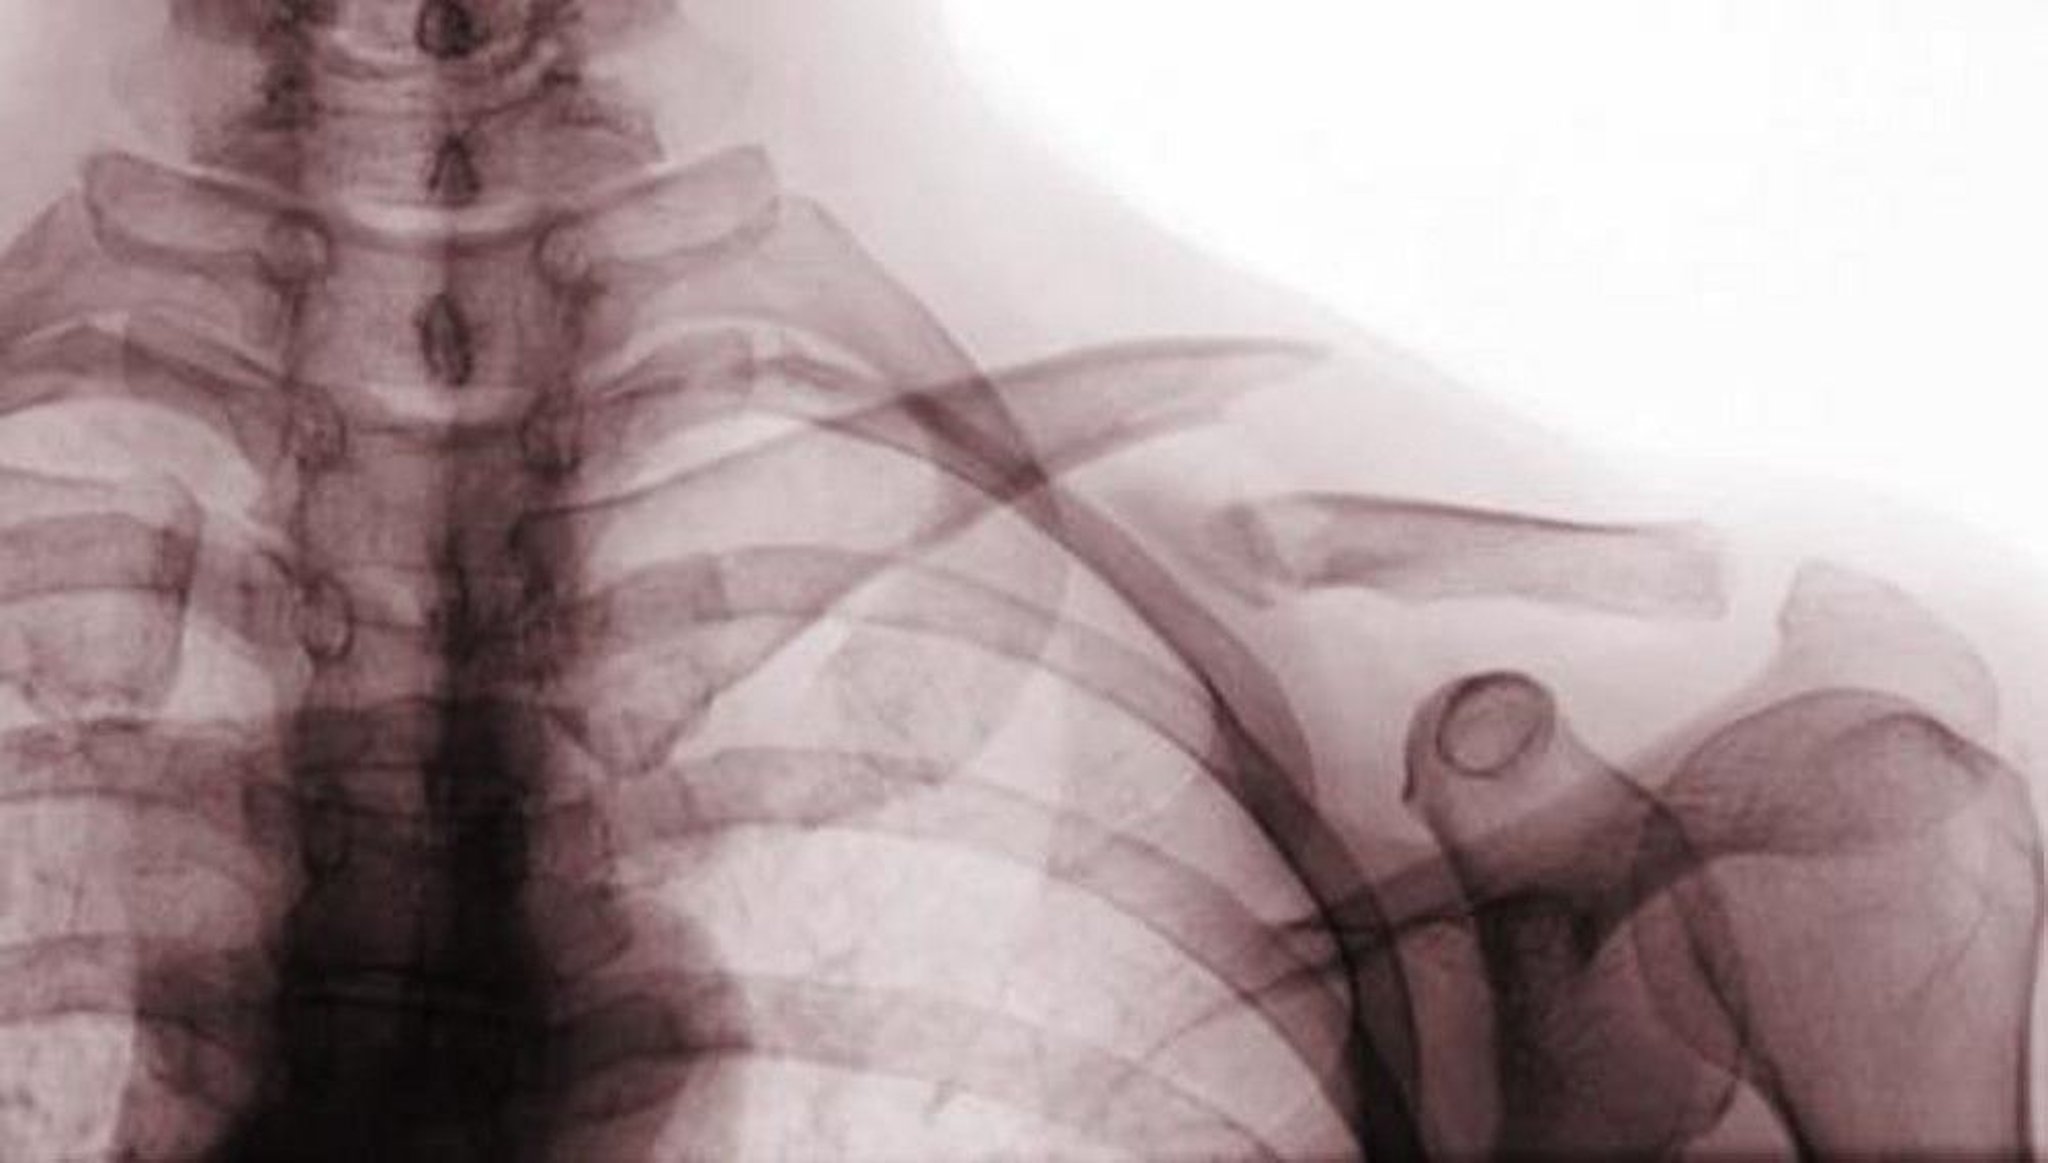

This anteroposterior radiograph view shows a displaced fracture of the middle third of the clavicle (class A fracture).

Scott Camazine/SCIENCE PHOTO LIBRARY